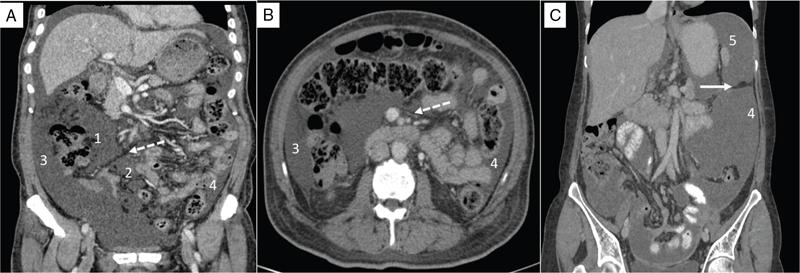

Shivsamb Jalkote, Slesha Bhalja, Disha Lokhandwala, Mansi Jantre, Karthik Ganesan Peritoneum is involved in a diverse group of primary as well as secondary pathologies ranging from the infective/inflammatory spectrum to malignancies. Peritoneal diseases are both common and potentially life threatening, and yet often get neglected in routine evaluation, due to the complex peritoneal anatomy and sometimes subtle imaging manifestations. The radiologist forms an integral part of the multidisciplinary team dealing with peritoneal pathologies and hence, having a lucid understanding of peritoneal anatomy, pathways of disease spread and different treatment options is paramount for an accurate radiological analysis. All three major serosal cavities (pleural, pericardial and peritoneal) of the body are derived from a single coelomic cavity, which is lined by a continuous mesothelium. At 2 weeks of gestational age, during the gastrulation stage, the embryo is a trilaminar disc, composed of the endoderm, mesoderm and ectoderm. During this stage, the development of the coelomic cavity commences as a consequence of morphological changes in the mesodermal cells leading to a coalition of the intercellular spaces. Peritoneum originates from mesoderm with its parietal layer developing from somatic mesoderm and visceral layer developing from splanchnic mesoderm. Initially, the peritoneum is an empty sac into which the growing gut tube protrudes (at 3 weeks of gestational age), resulting in the formation of the dorsal mesentery (formed by the fusion of two layers of the splanchnopleuric mesoderm) by which the gut tube is suspended lengthwise. The mesodermal cells opposed to the gut tube represent the future visceral peritoneum and those lining the body wall and the septum transversum form the future parietal peritoneum. Analogously, the ventral mesentery originates from the mesoderm of the septum transversum with the closure of the anterior abdominal wall, and, is short and not as extensive as the dorsal mesentery. The two mesenteries are aligned in the sagittal plane, subdividing the primitive peritoneum into right and left cavities, which are continuous anteriorly below the inferior edge of the ventral mesentery. With the development of various abdominal organs as buds from the gut tube, the capacity of the abdominal cavity diminishes, pushing the midgut loop into the umbilical cord. This physiologic herniation of the midgut takes place at the 6th week of gestation. Simultaneously, as the peritoneum drapes over the developing organs, there is compartmentalization of the cavity and a pattern of folds develops that eventually form the peritoneal ligaments. The majority of these ligaments arise from the ventral or dorsal mesentery. As the hepatic bud develops within the ventral mesentery, derivatives of the ventral mesentery can be divided based on their relation to the liver. The gastrohepatic ligament (lesser omentum) develops dorsally and the falciform, coronary, and triangular ligaments develop ventral to the liver. Conversely, the dorsal mesentery spans between the gut tube and the posterior abdominal wall, and the spleen and pancreatic tail develop within it. In congruence, it forms the gastrophrenic, gastrosplenic and splenorenal ligaments and peritoneal folds of the small and large intestines. As stated earlier, the dorsal mesentery has a relatively larger caudad extension and since the spleen develops in its upper portion, the rapidly growing mesentery beyond the spleen forms the greater omentum. Finally, the differential growth of the greater curvature of the stomach and the right hepatic lobe results in rotation of the abdominal organs and their mesentery, and the cephalad portion of the peritoneal cavity is divided into a larger ventral cavity, called the greater sac, which caudally communicates with the common peritoneal cavity, and a smaller dorsal cavity called the lesser sac. The key aspects of peritoneal development are summarized in Flowchart 8.6.1 and Fig. 8.6.1. Laparoscopy remains the gold standard in the assessment of peritoneal disease, however, it is an invasive technique, and has certain diagnostic limitations including the inability to assess parenchymal diseases, extraperitoneal diseases, and also has limited utility in the presence of adhesions. Hence laparoscopy is not recommended as the first-line modality and has been replaced by cross-sectional imaging in routine clinical practice. The role of imaging is primarily to assess disease burden in terms of volume and extent and to identify surgically nontreatable disease, which reduces open and shut laparotomies. Peritoneal metastatic disease burden is assessed using peritoneal carcinomatosis index (PCI) both surgically as well as using cross-sectional imaging, details of which will be discussed subsequently. CT, MRI and PET/CT are all commonly used imaging modalities, however, there is no singular universally accepted reference imaging standard for the peritoneal disease. In a recent meta-analysis evaluating the diagnostic performance of imaging in the detection of peritoneal metastasis (PM), authors concluded that MRI (DWI) and PET/CT show comparable diagnostic performance in gastrointestinal and ovarian cancer malignancies however the widespread availability of MRI makes it the more likely imaging modality of choice in the future. The results of this study are summarized in Table 8.6.1. Conventional imaging including radiography and barium studies have a poor diagnostic yield in evaluating peritoneal pathologies. Abdominal radiographs are usually restricted for identifying pneumoperitoneum and bowel obstruction in the setting of acute abdominal pain. Diffuse increase in radio-opacity of the abdomen, poor definition of soft tissue shadows (psoas, liver and spleen), bulging flanks along with medial displacement of small bowel loops from the properitoneal fat stripe are indirect markers of large ascites which can prompt further evaluation with ultrasonography. Indirect features of peritoneal disease on barium studies include mass effect and displacement of adjoining bowel loop, narrowing of bowel loop with bowel dilatation along with nodularity, spiculation, or tethering of adjacent mucosal folds or haustra with sacculation of the uninvolved contralateral border. Barium studies have fallen out of favour in routine radiological practice owing to the widespread use of cross-sectional imaging. Ultrasonography (US) is a readily available and relatively inexpensive imaging tool. Traditionally its role in the evaluation of peritoneal pathologies is limited as US beam gets strongly reflected at the interface of air and visceral structures which leads to obscuration of underlying structures. US remains the primary imaging modality in the evaluation of an acute abdomen and is useful in detecting of ascites, focal lesions and any focal abnormality at the site of tenderness. US has the unparalleled advantage of providing real-time assistance in performing imaging-guided procedures such as paracentesis and peritoneal biopsies. US can be used in characterization of focal lesions (as solid, solid-cystic and cystic) and assessment of internal vascularity using colour Doppler. Transvaginal US provides a good overview of pathologies involving pouch of Douglas besides the uterus and adnexa. Experienced and skilled sonologists can detect omental thickening, peritoneal nodules and small surface deposits using high-frequency transducer (Fig. 8.6.2). Endoscopic US allows assessment of diseases involving peritoneal ligaments besides assistance in a guided biopsy. The reported sensitivity, specificity and accuracy of EUS-FNA versus CT/MRI in detecting PM was 91% versus 28%, 100% versus 85% and 94% versus 47%, respectively. CT is the most commonly employed imaging modality in the evaluation of peritoneal pathologies due to its widespread availability, fast acquisition and high spatial resolution. Current generation multidetector CT scanners (64 slices and above) offer very thin collimation, leading to the acquisition of near isotropic volumetric data which allow reformations in coronal and sagittal images without any added imaging time. It is the modality of choice for preoperative staging in most primary abdominal and pelvic malignancies (e.g. stomach, appendix, ovary) owing to its ability to detect local and regional infiltration, nodal involvement and distant metastases. CT is also used to evaluate PCI and detect disease in critical and occult locations, thus significantly altering further management strategies. CT is the most common imaging modality used in postoperative surveillance and evaluation of postoperative recurrence. CT protocol includes administration of both enteric contrasts (oral and rectal) and intravenous contrast (Table 8.6.2). Optimal bowel distension is key as collapsed loops can mimic disease and also mask the serosal and endoluminal disease. Often, a CT scan of the chest is performed as an adjunct to rule out pleuroperitoneal/transdiaphragmatic dissemination. Helical (≥64 slice scanner) Dual energy scanner if available As thin as possible (≤1 mm) Same as section thickness without gap From xiphisternum to pubic symphysis Chest included if suspicion of thoracic involvement 1 L of positive oral contrast over duration of 60 minutes and 500 mL of positive rectal contrast on table before administration of IV contrast 1.5–2 mL/kg of nonionic contrast with high iodine concentration (≥ 300) at rate of 3–5 mL/sec Unenhanced imaging not recommended. Monophasic acquisition at 60 seconds usually sufficient in majority cases Arterial phase at 20 seconds acquired for arterial assessment Delayed phase in cases of ureteric obstruction, slow bowel transit and suspected leak. Axial 1 mm thickness, multiplanar reformats in coronal and sagittal planes at 1 mm MIP or 3D volumetric sections for vascular assessment There is a wide range of reported diagnostic accuracy (sensitivity ranging from 25% to 100%, specificity ranging from 78% to 100%) of CT in the assessment of PM depending on the expertise of the reader and scanner type. In general, key factors affecting CT sensitivity include the size of lesion, the region of affection and presence of ascites. 64 slice scanners with multiplanar reformations allow 100% sensitivity and positive predictive value in detecting lesions measuring >5 cm, which partly diminishes for lesions between 0.5 cm and 5 cm in size with sensitivity and positive predictive being 83% and 93%, respectively. It receives the most criticism in the evaluation of lesions < 0.5 cm with significantly low sensitivity and positive predictive value (43% and 76%, respectively). There is also a great degree of variation in sensitivity based on the anatomical location of the disease. In a study by Koh et al., the detection rates ranged from 8% to 67%, depending on the region involved; only the epigastrium exceeded 60%, with the small-bowel disease being the most poorly visualized (8%–14%). The sensitivity for tumour detection in epigastrium, greater omentum and under surfaces of the diaphragms was 60%–90%, while it was 50%–70% in the retroperitoneum and pelvis, and small bowel-mesentery involvement was detected in merely 20%–50% of cases. These are noteworthy findings, as small-bowel involvement has major implications on outcome and is one of the limiting factors for complete cytoreduction. Poor soft tissue resolution of CT doesn’t allow accurate differentiation between mucinous deposits from ascites. Administration of positive enteric contrast can mask calcified serosal deposits. DECT uses two separate x-ray energy spectra and allows characterization of tissues based on their differences in attenuation properties at different energies. Though the role of DECT in the assessment of abdominal pathologies is increasingly reported in the literature, there are very limited data available on its application in assessment of peritoneal pathologies. The combination of iodine overlay with conventional imaging has shown a better specificity in differentiating PM from benign peritoneal entities, and hence can be particularly useful in the postoperative setting. MR imaging offers excellent soft tissue resolution, multiplanar capabilities and avoids exposure to ionizing radiation, making it an attractive tool for evaluation of peritoneal diseases. MRI is better suited and can be problem solving in visualization of smaller lesions (<1 cm) and assessment of relatively concealed areas such as subphrenic, mesenteric and bowel serosa. Unenhanced T1- and T2-weighted images can show larger peritoneal deposits and masses but are relatively insensitive for the depiction of smaller lesions. The combination of diffusion-weighted imaging (DWI) and delayed gadolinium-enhanced MR imaging is considered the most accurate technique for detecting peritoneal tumours (Fig. 8.6.3). MRI protocol for assessment of peritoneum has been detailed in Table 8.6.3. In a study by Low RN et al., MRI PCI correctly categorized tumour volume in 91% of patients compared to surgical PCI, as opposed to 50% with CT. In addition, MRI demonstrated per site sensitivity of 95%, specificity of 70% and accuracy of 88%, while CT showed a corresponding per site sensitivity of 55%, specificity of 86% and accuracy of 63%. MRI PCI has also shown to have better prediction of intraoperative burden of disease for invasive appendiceal and peritoneal mesothelioma histologies as compared to CT-PCI. *This general imaging protocol is based on 3 T MRI Siemens system, covers both abdomen and pelvis. Protocol is modified depending on primary disease and type of scanner. Low RN. Preoperative and surveillance MR imaging of patients undergoing cytoreductive surgery and heated intraperitoneal chemotherapy. Journal of gastrointestinal oncology. 2016 Feb;7(1):58. The higher cellularity of majority of peritoneal nodules results in restriction of water movement and corresponding high signal intensity on DW images. On the higher b-value images, bowel contents are suppressed and the serosal and peritoneal tumours become hyperintense. DWI is also useful to demonstrate associated lymphadenopathy, hepatic and osseous metastases. In a study by Zhang et al., in PC of colorectal carcinoma, DWI demonstrated sensitivity of 69.4%, 91.3% and 100% for lesions measuring <0.5 cm, 0.5–5.0 cm and >5 cm, respectively. The overall sensitivity, specificity and accuracy of DWI for the detection of peritoneal tumours were 80.3%, 84.5% and 82.1%, respectively. DWI/MRI is also superior in demonstrating lesions involving small bowel wall, with an accuracy of 92%–95% versus 48% for CT. Reported negative predictive value of DWI for small bowel serosal metastases is 100%. Whole-body DWI/MRI was highly accurate for the prediction of inoperability (PPV 100%, NPV 90.3%) and was capable of detecting metastases both inside and outside the abdominal cavity. Peritoneal tumours enhance slowly and are best depicted on the final set of images obtained about 5 minutes following gadolinium administration. The increased conspicuity of these enhancing peritoneal tumours improved detection of small tumours that are often missed on CT scans. For this reason, perfect breathhold is essential while obtaining the final set of images and if images are acquired later, contrast that has diffused into the ascitic fluid can obscure smaller lesions. The high-contrast conspicuity of fat-suppressed and delayed gadolinium-enhanced MRI makes it the imaging modality of choice in depicting subcentimetre deposits (including those measuring <5 mm), and also deposits in anatomically concealed sites (e.g., subphrenic, mesenteric and bowel serosa). Gadolinium-enhanced MRI has higher sensitivity in detecting peritoneal lesions <1 cm which is about 85%–90% compared to 22%–33% for CT. Despite the clear superiority of MRI over CT, the major detractors against MRI are the long exam times and the higher expense burden. Longer acquisition times can lead to motion artefacts related to respiration and bowel peristalsis compromising detection of smaller lesions. MRI is contraindicated in patients with pacemakers, cochlear implants and claustrophobic patients with some exceptions. DW-MRI is less sensitive in special histological subtypes such as signet ring cell and mucinous adenocarcinoma due to their limited restricted diffusion. The combined use of FDG-PET with anatomical CT imaging, provides the added benefit of qualitative and semiquantitative metabolic analysis (Fig. 8.6.4). PET/CT has an established role in staging of most of the primary tumours of the chest, abdomen and pelvis. It is also helpful in assessing malignant ascites or PM of an unknown primary. In disseminated malignancies, it can localize the optimal site for biopsy depending upon metabolic activity of the lesion. PET/CT should be used selectively in preoperative assessment of patients with large tumour volumes and poor prognostic histologies being considered for CRS and HIPEC to rule out extra abdominal metastases. It can also detect extraabdominal metastases, including mediastinal and supraclavicular nodes, and other organ sites, such as bone and brain. It can also detect nodal involvement in normal-sized lymph nodes seen on conventional cross-sectional imaging. PET/CT also plays a role in disease surveillance and assessment of response to neoadjuvant chemotherapy. This is particularly relevant in malignancies where anatomical changes are so small that measurement of size change alone becomes unreliable and also in differentiating between residual/recurrent disease and postoperative changes after CRS and HIPEC. Besides oncological indications, PET/CT is also helpful in assessment of benign and inflammatory diseases to evaluate disease extent and also localize the site for biopsy. In cases of pyrexia of unknown origin, PET/CT has often been employed to demonstrate unsuspected peritoneal disease. Utility of PET/CT in peritoneal disease assessment is limited in developing counties due to its higher cost burden and lower accessibility. Certain histological subtypes such as mucinous and signet ring cell carcinomas show low FDG uptake making PET/CT less sensitive. Low metabolic uptake in these subtypes is thought to be due to low tumour cell density, higher content of metabolically inert mucin and lack of expression of glucose transporter Glut-1. This is more relevant in context of colorectal malignancy where mucinous carcinoma and signet ring cell carcinoma more frequently metastasize to the peritoneum compared to adenocarcinoma (48%, 51% and 20%, respectively). PET/CT is prone to artefacts caused by misregistration between the CT and PET images which can lead to inaccurate assessment of certain regions such as dome of diaphragm and structures adjoining the urinary bladder, making the detection of pelvic implants difficult due to partial volume effects. Implants against the small bowel and mesentery may be obscured by the physiological metabolic activity of bowel. Pretreatment PET/CT demonstrates a higher accuracy than CT for nodal and metastasis staging but has limited sensitivity to detect PM, especially when there is small-volume disease as only 13.6% of the nodules less than 0.5 cm were correctly identified by PET/CT. Table 8.6.4 summarizes role of different imaging modalities for assessment of peritoneal diseases. Peritoneum is the largest serosal membrane in human body with surface area of about 2.2 m2. It is composed of parietal and visceral layers which are continuous with each other, with parietal peritoneum lining the coelomic cavity and visceral peritoneum lining the visceral organ (Fig. 8.6.5). The peritoneum essentially minimizes friction, resists infection and stores fat, allows free movement of the abdominal viscera which gets restricted in presence of adhesions. Peritoneum acts as first line of defence in controlling disease spread, and, it exudes fluid and cells in response to injury or infection (peritonitis), to wall off or localize infection. In natural states, intraperitoneal spread of infection is limited by lymphoid aggregates and stomata on both the peritoneal layers. Omentum is commonly known as policeman of abdomen as it migrates to the site of infection and isolates affected area from healthy tissues. Iatrogenic violation of peritoneum following surgery can lead to recurrence along the operative incision scar sites and along the vaginal cuff following hysterectomy in pelvic malignancies. The parietal peritoneum is supplied by nerves (e.g. phrenic and thoracoabdominal) to the adjacent body wall, and is predominantly very sensitive to pain, which explains the typical referred shoulder pain from upper abdominal pathologies such as gall stones and pancreatitis. The visceral peritoneum is insensitive to pain and responds mainly to stretching. These two layers encompass a potential space, called the peritoneal cavity which contains approximately 50–75 mL of clear serous fluid. Peritoneal cavity is a closed space in males while in females it communicates with extraperitoneal pelvis through ostia of fallopian tubes allowing transport of ovum. This communication serves as natural route for ascending spread of sexual transmitted disease from genital organs into peritoneal cavity leading to pelvic inflammatory disease and uncommonly perihepatitis (Fitz–Hugh–Curtis syndrome). The invaginations of the peritoneum result into formation of three different types of structures namely ligaments, omentum and mesentery (Figs. 8.6.6–8.6.9) which serve as bridges that permit blood, lymph vessels and nerves to reach the viscera. Ligaments are double folds of peritoneum that connect one organ to another organ or to the abdominal wall and are named usually after the respective viscera. The liver, for example, is connected to the diaphragm by the falciform ligament, coronary ligament and right and left triangular ligaments. Mesenteries are double folds of peritoneum that suspend intestine to the posterior abdominal wall (retroperitoneum) such as the small bowel mesentery, transverse and sigmoid mesocolon. Omentum are double folds of peritoneum that extends from the stomach to other organs and include the greater and lesser omentum. Table 8.6.5 summarizes the peritoneal ligaments in abdomen and pelvis. In medical school days, the anatomy textbooks traditionally divided abdomen and pelvis into tricompartmental model comprising of peritoneal cavity, retroperitoneum and extraperitoneal spaces. This model is good for basic understanding of anatomy and confinement of certain disease processes but fails to explain spread of diseases from retroperitoneum to peritoneum besides spread of some disease processes within peritoneal cavity itself. Considering these shortcomings of conventional description of anatomy, the unifying concept of subperitoneal space has evolved in literature and is getting accepted increasingly. As per this concept, abdomen and pelvis are divided in two spaces peritoneal cavity and subperitoneal space which are separated from each other by peritoneum. Subperitoneal space (Fig. 8.6.10) is large anatomically continuous potential space which connects peritoneal cavity with retroperitoneum. It constitutes the subserosal areolar tissue and fat tissue lining the inner surfaces of the peritoneum and the abdominopelvic musculature. The omentum, ligament and mesentery are the interconnecting peritoneal folds building the subperitoneal space. All the abdominal and pelvic organs along with their vascular, lymphatic and nervous supplies are situated within subperitoneal space. With this concept, we want to correct the common misconception of intraperitoneal organs as in strict terminology there is no organ within the peritoneal cavity itself. It is imperial to understand differences between peritoneal and subperitoneal spaces as these are mutually exclusive spaces having distinct patterns of disease spread which we will discuss in subsequent sections. In resting state, peritoneal cavity is collapsed and thus not visible on routine imaging. Peritoneal cavity usually gets distended due to disease processes composed of fluid, air or masses. The peritoneal cavity is divided into two parts: the greater sac and the lesser sac which communicate with each other via an epiploic foramen (of Winslow). The greater sac forms main peritoneal cavity and extends from the diaphragm down into the pelvis. The lesser sac is small diverticulum and lies between stomach and pancreas. For better understanding, abdominal peritoneal cavity is divided into supra- and inframesocolic compartments, communicating with pelvic peritoneal cavity which is further divided by other peritoneal folds and reflection (Flowchart 8.6.2, Figs. 8.6.10 and 8.6.11). Supramesocolic compartment (Fig. 8.6.12) is situated between the diaphragm and transverse mesocolon. It is arbitrarily divided into right and left supramesocolic peritoneal spaces, which can be further subdivided into a number of subspaces by upper abdominal organs and peritoneal ligaments. Right supramesocolic space is divided into three subspaces: right subphrenic space, right subhepatic space and lesser sac. Right subphrenic space is partially separated from right subhepatic space by right triangular ligament. Right subphrenic space is situated between right hemidiaphragm and right lobe of liver (superior, anterior and right lateral surfaces). It is limited posteriorly by the coronary ligament and medially by the falciform ligament with the latter separating it from the left subphrenic space. Right subhepatic space is situated inferior to right lobe of liver and has anterior and posterior components. Anterior component is limited inferiorly by transverse mesocolon whereas the posterior component extends anterior to right anterior perirenal fascia. Posterior component of right subhepatic space is commonly known as hepatorenal pouch (of Morrison) and forms most dependent site in supine position, thus being a common site of fluid accumulation. The right subhepatic space freely communicates with right subphrenic space superiorly and right paracolic gutter inferiorly. Lesser sac (also known as omental bursa) is situated superior to the transverse mesocolon, anterior to pancreas and posterior to the lesser omentum, stomach and gastrocolic ligament. Lesser sac (Fig. 8.6.13) communicates with right subhepatic space (of greater sac) via epiploic foramen which is bounded by IVC posteriorly, free margin of hepatoduodenal ligament anteriorly, D1 (first part of duodenum) caudally and caudate lobe of liver rostrally. Division of lesser sac into smaller superior compartment (superior recess) and larger inferior compartment (inferior recess and splenic recess) is accomplished by prominent crescentic gastropancreatic fold (peritoneal fold overlying common hepatic and left gastric artery) which extends from neck of the pancreas to the upper part of lesser curvature of stomach. The superior recess is situated to the right of midline above pancreas and posterior to lesser omentum. It surrounds the medial aspect of the caudate lobe and superiorly into the fissure for the ligamentum venosum. Splenic recess extends to splenic hilum, and is limited by gastrohepatic ligament (anterior), gastrosplenic ligament (lateral) and splenopancreatic ligament (posterior). Inferior recess is located to left of midline, separates stomach from the pancreas and transverse mesocolon. In few cases, an infrapancreatic part can be seen due to persistence of inferior recess within the greater omentum or due to downward bowing of transverse mesocolon. Left supramesocolic space is wider than right supramesocolic space and is limited above by left hemidiaphragm and below by transverse mesocolon and phrenicocolic ligament. Left supramesocolic space (subphrenic part) is medially separated from right supramesocolic space by falciform ligament and inferiorly from left paracolic gutter by phrenicocolic ligament. It is divided into four communicating subspaces: anterior left subphrenic space, posterior left subphrenic space, anterior left perihepatic space and posterior left perihepatic space. All these spaces communicate with each other. The definitions of the boundaries of these spaces vary in literature. Anterior left subphrenic space is situated between gastric fundus and left hemidiaphragm. Posterior left subphrenic space (also known as perisplenic space) surrounds spleen. Anterior left perihepatic space is situated between anterosuperior aspect of left lobe of liver and left hemidiaphragm. Posterior left perihepatic space (also known as gastrohepatic recess) is situated between inferior aspect of left lobe of liver and lesser omentum. Inframesocolic compartment (Fig. 8.6.14) extends below transverse mesocolon to the level of pelvic brim and is divided into large central part and smaller paracolic part (lateral recesses). Central portion of inframesocolic compartment is unequally divided by obliquely oriented small bowel mesentery leading to formation of smaller right inframesocolic compartment and larger left inframesocolic compartment. Right inframesocolic space terminates at the ileocaecal junction and does not communicate with pelvis. Left inframesocolic space is in communication with pelvic peritoneal spaces except at the sigmoid mesocolon attachment which offers partial barrier. Peritoneal recesses on the posterior abdominal wall lateral to the ascending and descending colon form right and left paracolic gutters respectively. Both paracolic gutters communicate freely with pelvic peritoneal spaces. Right paracolic gutter is deeper than left gutter and is in free communication with right supramesocolic space. Left paracolic gutter is partially limited from left supramesocolic space due to presence phrenicocolic ligament. Pelvis constitutes about one-third of the total volume of the peritoneal cavity and is most dependent part in both supine and erect positions. Inferiorly peritoneum drapes over fundus of urinary bladder, anterior and posterior surface of uterus and upper posterior vagina in females and anterolateral surface of the upper rectum leading to formation of different peritoneal spaces. The urinary bladder subdivides pelvis into anterior and posterior paravesical spaces. The anterior paravesical space is further compartmentalized by remnant of the urachus (median umbilical ligament), the obliterated umbilical arteries (medial umbilical ligament), and the lateral umbilical ligaments (inferior epigastric vessels) into five fossae: the right and left lateral and medial inguinal fossae and the supravesical fossa. The supravesical space is seen in midline with medial and lateral inguinal fossae placed on either side. The supravesical space lies above urinary bladder between the two medial umbilical folds, is usually occupied by small bowel loops and fundus of distended urinary bladder. Just lateral to the supravesical space is the medial inguinal fossa, located between the medial and lateral umbilical folds. The femoral ring is located inferolaterally and hence ascitic fluid in the medial inguinal fossa can extend into the femoral canal. Finally, the lateral inguinal fossa is located between the lateral umbilical fold and parietal peritoneum (which reflects over the vas deferens or round ligament). It usually contains the cecum or ileum on the right and sigmoid colon on the left. Extension of ascitic fluid into the inguinal canal can occur through the deep inguinal ring, located anteromedial to the lateral inguinal fossa. The posterior paravesical space is a larger recess situated between the urinary bladder and rectum. In women, uterus further divides it into smaller vesicouterine and larger rectouterine spaces. The vesicouterine space is located between the urinary bladder and uterus and is formed as the peritoneum drapes the uterine body and fundus and then runs over the urinary bladder (along its posterosuperior surface). It is continuous with the supravesical space anteriorly and its depth varies with the degree of urinary bladder distension. The rectouterine pouch (of Douglas) is delimited anteriorly by the uterus and broad ligaments and posteriorly by the rectum. Lateral to this cul-de-sac on either side are the uterosacral ligaments that run from the sacrum to the uterine cervix that separate the rectouterine pouch from the laterally located ovarian fossae. In men, the rectovesical pouch is formed as the peritoneum runs from the rectum to the posterior surface of the bladder. Posteriorly, the peritoneal reflection from the upper rectum runs to the pelvic sidewalls, forming right and left pararectal fossae, which vary in size with the degree of rectal distension. Analogous to the uterosacral ligaments in women, the rectovesical space is restricted by sacrogenital folds on either side, which extend from the urinary bladder to the sacrum. The rectovesical space and rectouterine space (pouch of Douglas) form most dependent areas in both in supine and standing positions in males and females, respectively (both in supine and standing positions). The key aspects of pelvic peritoneal spaces are summarized in Flowchart 8.6.3, Figs. 8.6.15 and 8.6.16. Peritoneal recesses represent small pockets or fossae in the peritoneal cavity bounded by folds of peritoneum and possibly represent developmental aberrations. Knowledge of these recesses is important as they can serve as pathways for internal hernias. Multiple peritoneal folds may surround fourth part of duodenum (D4) and duodenojejunal junction forming duodenal recess. Six major duodenal recesses include superior, inferior, paraduodenal, retroduodenal, duodenojejunal and mesentericoparietal recess. The superior duodenal recess is situated to the upper left side of fourth part of duodenum (D4) behind the superior duodenal fold at L2 level. Inferior mesenteric vein is situated behind lateral end of superior duodenal fold. Inferior duodenal recess is situated on left of D4 below DJ flexure and behind the inferior duodenal fold at L3 level. Inferior duodenal recess often exists in association with superior duodenal recess. Reported incidence of superior and inferior duodenal recesses is about 40%–50% and 70%–75%, respectively. Paraduodenal recess is seen on left side and slightly behind D4 bounded anteriorly by paraduodenal (falciform fold). Right free margin of paraduodenal fold contains the inferior mesenteric vein and an ascending branch of the left colic artery. This recess is seen in about 2%–3.8% cases and is site for left paraduodenal hernia. Retroduodenal recess as the name suggests situated behind the third and fourth parts of the duodenum and in front of abdominal aorta. Its orifice is bounded anteriorly by duodenoparietal fold. Retroduodenal space is largest among all the duodenal recesses and is seen in about 2.5% cases. Duodenojejunal recess is situated between the duodenojejunal flexure and root of transverse mesocolon, hence also known as mesocolic recess. Its boundaries include pancreas (superior), left renal vein (inferior) and left kidney (left). Its opening lies between two peritoneal folds, is directed inferiorly and to the right. Duodenojejunal recess is seen in about 20% cases and is almost never associated with other duodenal recesses. Mesentericoparietal recess is situated below third part of duodenum and behind the upper part of the mesentery. Its opening is bounded anteriorly by the fold of mesentery raised by the superior mesenteric artery. This recess is most rare among all with incidence of about 1%. It is the site for right paraduodenal hernia. The key aspects of duodenal recesses are summarized in Table 8.6.6 and Fig. 8.6.17. Peritoneal folds adjoining cecum result in formation of four main recesses: superior ileocaecal recess, inferior ileocaecal recess, retrocaecal recess and paracolic recess (Fig. 8.6.18). Surgically these recesses are important as they can be sites for internal herniation (except for paracolic sulci) or site of abscess formation in complicated appendicitis. Superior ileocaecal recess is bounded in front by the vascular fold of the cecum (containing anterior caecal vessels), behind by the ileal mesentery, below by the terminal ileum and on the right by the ileocaecal junction with its opening on left. Inferior ileocaecal recess is bounded in front by the ileocaecal fold (bloodless fold of Treves), above by the terminal ileum and its mesentery, to the right by the caecum, and behind by the upper part of the mesoappendix with its opening on left. Retrocaecal recess is bounded in front by posterior wall of cecum (and sometimes the proximal ascending colon), behind by the parietal peritoneum (posterior abdominal wall), and on either side by two caecal folds (parietocolic folds). Retrocaecal recess is largest among all the caecal recesses with its opening inferiorly and often contains appendix. Paracolic sulci represent variable one or more shallow lateral depressions in the peritoneum investing the cecum usually within the right paracolic gutter. This recess lies behind and inferior to the apex of inverted V-shaped root of sigmoid mesocolon with orifice opening inferiorly. Posteriorly, it is limited by parietal peritoneum of covering the left ureter at its iliac vessel crossing. This recess can be variable in size ranging from dimple to a small fossa in majority of the cases usually admitting little finger. It forms most common site of sigmoid mesocolon hernia. It can also be involved by peritoneal fluid and metastatic disease. Peritoneal and subperitoneal spaces are mutually exclusive spaces having distinct patterns of disease spread. Different pathways of the intraabdominal and extraabdominal disease spread are summarized in Table 8.6.7.